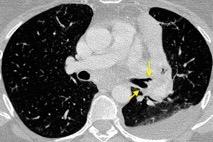

En el normal, el bronquio intermediario (BI) aparece en la proyección lateral, como una línea fina vertical que cruza el bronquio del LSI en su unión con el principal. (BPI) Engrosamiento del bronquio intermediario (BI)

97% de normales

Causas

Fallo cardiaco

Ca de pulmón

Metástasis

Linfoma

Sarcoidosis

Castleman

Schnur MJ et al.. Thickening of the Posterior Wall of the Bronchus Intermedius. Radiology. 1981

MJ et al.. Thickening of the Posterior Wall of the Bronchus Intermedius. Radiology. 1981 Ca. microcítico